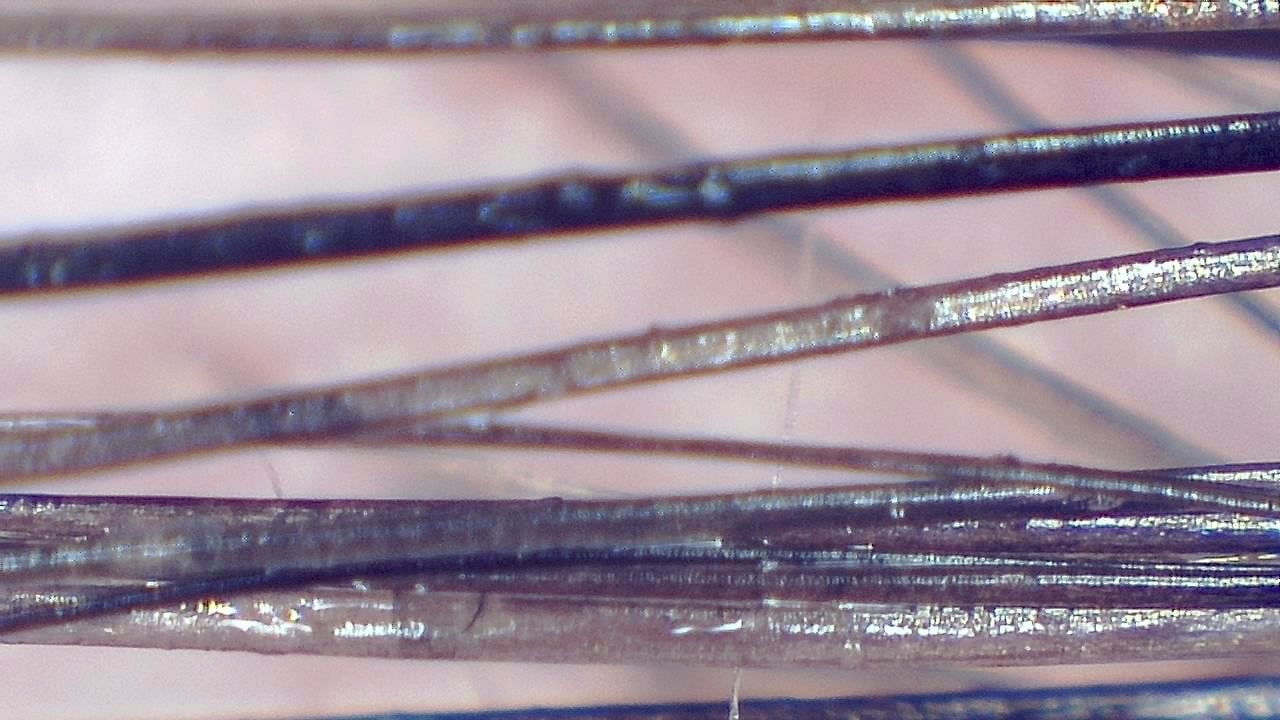

It is possible to visualize yellow dots, vellus hairs, follicular miniaturization, and other key dermoscopic markers used in the differential diagnosis of androgenetic alopecia, alopecia areata, and scarring alopecias.

- Visual estimation of follicular density and hair shaft thickness

- Longitudinal documentation to evaluate treatment efficacy

- High-quality images for reports and patient communication